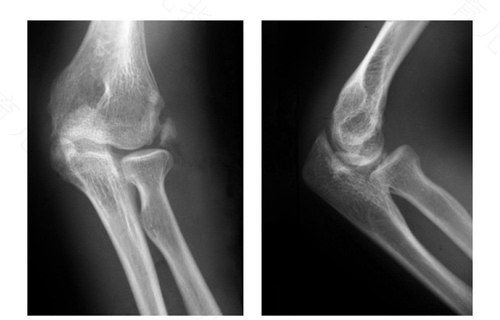

1、肱骨骨折常生于肱骨外科颈、肱骨干、肱骨髁上、肱骨髁间、肱骨外髁、肱骨内上髁。其中,尤以前三者为多,可发生于任何年龄。多由直接暴力或者是间接暴力所引起,如重物撞击、挤压、打击及扑倒时手或肘部着地,暴力经前臂肘部传至各部位。X线检查可诊断,并提示骨折的类型。

2、肱骨骨折可由暴力或间接暴力引起,直接暴力常由外侧击打肱骨干中份,致横形或粉碎形骨折。间接暴力常由于手部着地或肘部着地,力向上传导,加上身体倾倒所产生的剪式应力,导致中下三分之一骨折,有时因投掷运动或掰腕”也可导致中三分之一骨折。